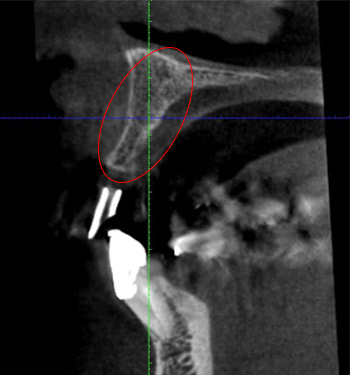

赤丸の部位のCT検査像です。骨が先細りしているのがわかります。